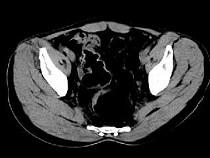

问题 女,51岁,腹胀、腹痛、进行性消瘦,影像检查如下图,最佳诊断是()

选项 A.乙状结肠Crohn病 B.乙状结肠结核 C.乙状结肠癌 D.乙状结肠淋巴瘤 E.乙状结肠息肉

答案 C